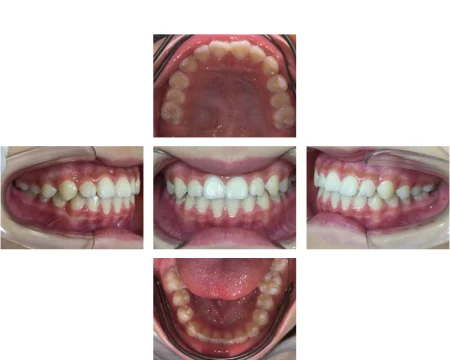

拝見すると、上下の前歯同士が噛み合っている「切端咬合(せったんこうごう)」と、前歯から奥歯までの歯並びが狭くなっている「歯列弓の狭窄(しれつきゅうのきょうさく)」の状態でした。そのため、将来ガタガタの歯並び「叢生(そうせい)」になることが予想できました。

そのため舌と顎の正常な発育をサポートし、口周りの筋肉を鍛え悪い癖を改善させる取り外し可能なマウスピース「マイオブレース」を使用していただき、正常な上下前歯の噛み合わせになるようにしました。

その後歯並びを横に広げる「床矯正」で叢生の改善を試み、歯の生え変わりの時期と重なったため永久歯がきれいに並ぶようにしっかりと観察して治療を進めていきました。